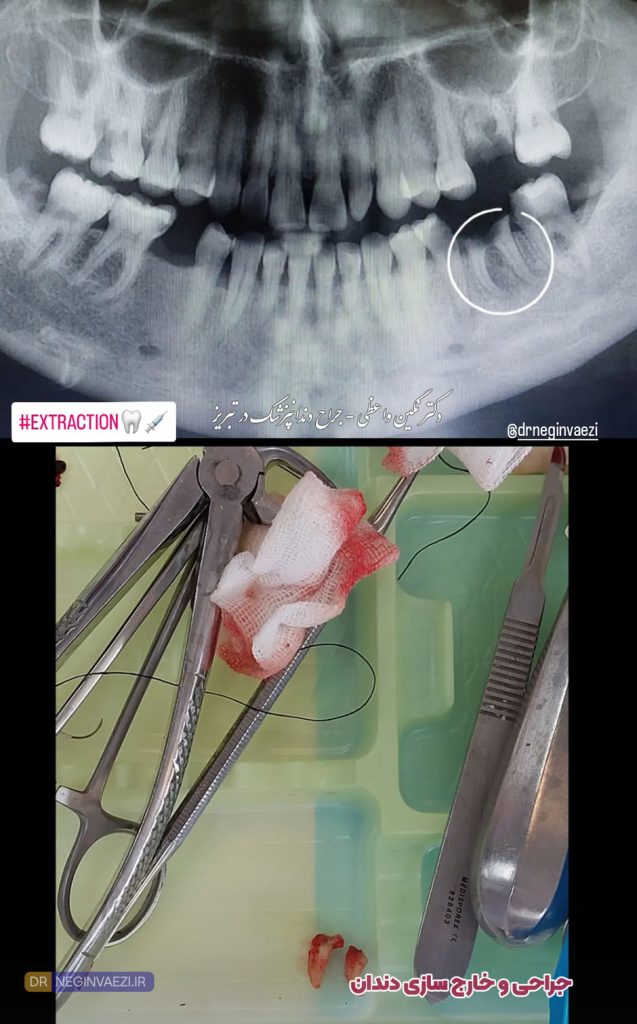

عکس جراحی دندان عقل فک پایین

عکس جراحی دندان عقل نیمه نهفته

عکس کشیدن دندان عقل

آیا برای جراحی دندان نیاز به عکس رادیوگرافی می باشد؟

بله! دندانپزشک قبل از هرگونه جراحی اعم از دندان عقل یا ریشه دندان، عکس رادیوگرافی تجویز خواهد کرد و پس از آن اقدام به کشیدن و یا جراحی خواهد نمود.